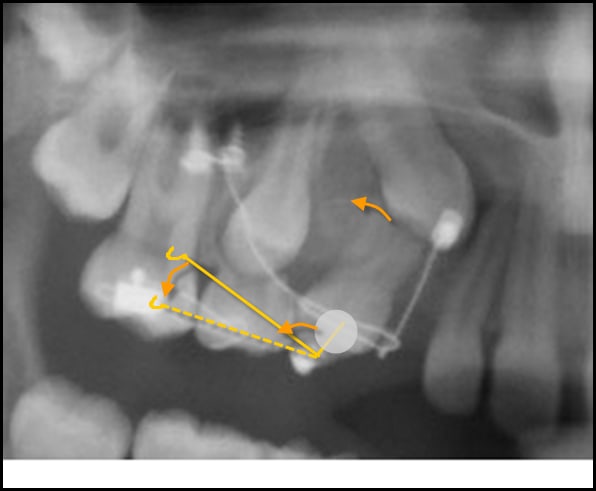

Donc pour éviter l'intrusion de la 14 je rajoute une ligature en stainless steel relier a la 14 ( danchemon ou clit) et a la boucle du ressort en eligoy au niveau de la boucle le reliant au fil en TMA. Vue que la ligature est non extensible dés que la 14 commencerait une intrusion une force extrusive compensatoire s'exercerait immédiatement due a la mise sous tension du fil TMA.

Alors, si tu pars avec un système de mécanique comme celui-là, il y a encore plus simple, en mettrant la 14 en intermédiaire :

- le bras qui sort de la 14 en distal et qui passe en occlusal pour exercer une force anti-horaire, tu peux l'accrocher directement sur la ligature reliée à la canine après avoir décroché le CT8. C'est lui qui le remplacera pour exercer la traction canine.

- et tu pourra utiliser le CT8 libéré pour empêcher l'ingression de la 14.

Seuls soucis avec ta proposition :

- le difficile contrôle de la force de traction et celui de sa direction.

- le contrôle de la situation verticale de la 14, elle est en occlusion, il ne faudrait pas qu'elle s'égresse plus..